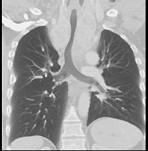

男,67岁,呼吸困难半余余,请结合影像学检查,选出最可能的诊断 ( )A.胸骨后甲状腺肿B.淋巴瘤C.间皮囊肿D.纵隔畸胎瘤E.胸腺瘤

选项 A.胸骨后甲状腺肿 B.淋巴瘤 C.间皮囊肿 D.纵隔畸胎瘤 E.胸腺瘤

答案 A